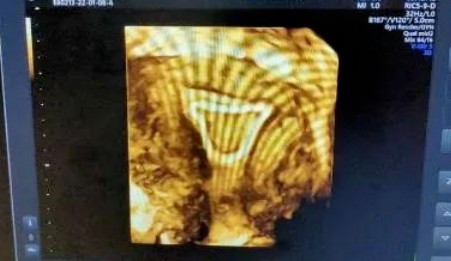

360°立体动态成像技术可清楚地显示子宫情况、输卵管形态、输卵管积水、通畅情况、伞端是否与周围组织粘连,大大提高输卵管的显示率和准确性;还能全方位立体动态地观察到胎儿生长发育状况。